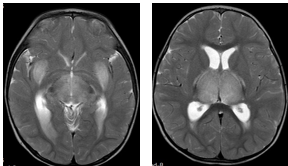

一例流感相关的急性坏死性脑病

图:患儿的头颅MR显示典型的急性坏死性脑病表现

神经系统并发症:流感可以导致脑病、脑炎、脑膜炎、脊髓炎、吉兰-巴雷综合征和急性坏死性脑病等。其中,急性坏死性脑病有较高的致残和致死率,需要特别警惕,多发生在流感起病后的12-72小时。